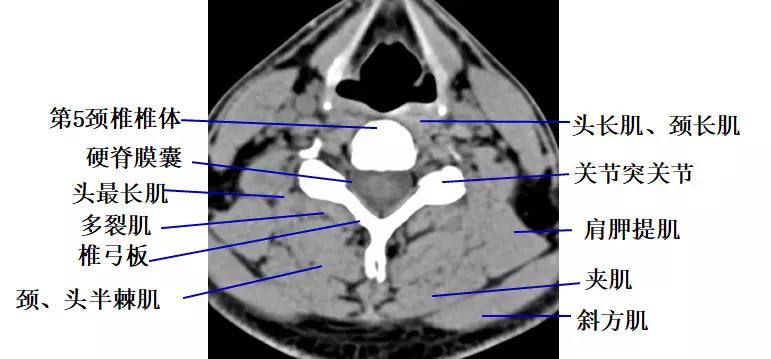

4.经颈椎椎体下部的横断层面(CT)